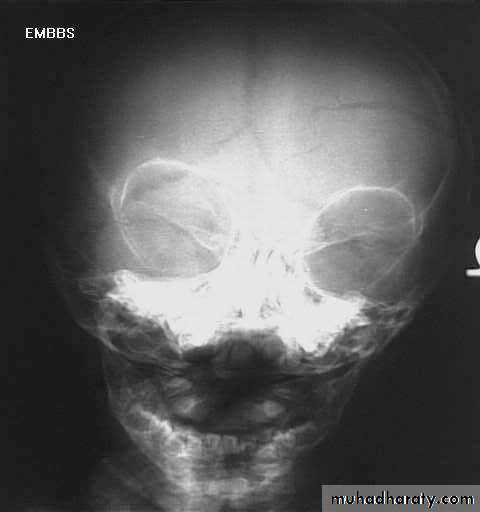

a. Plain skull x-ray

1. Can demonstrate the site and type of a skull fracture.2. A foreign body can also be seen.

Skull Fracture

Indications for skull x-ray in head injury